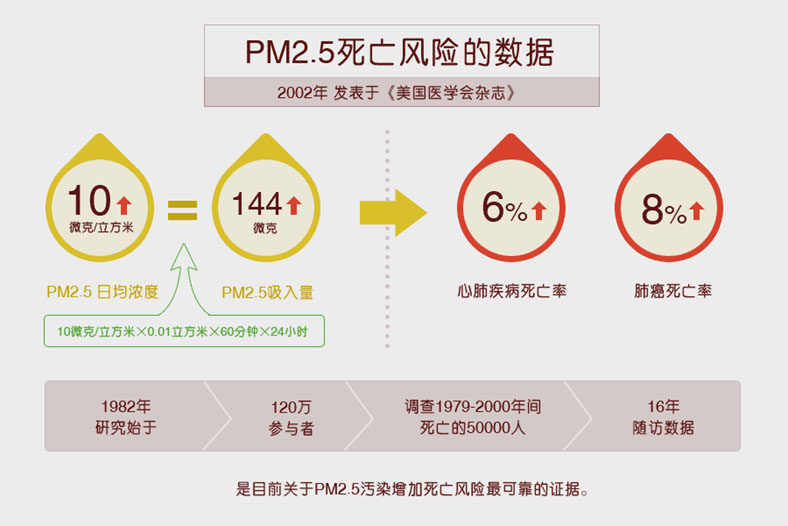

根据美国癌症协会和哈佛大学的研究结果,PM2.5 日均浓度每增加10微克/立方米,心肺疾病死亡率升高6%,肺癌死亡率升高8%。据此,世界卫生组织(WHO)於2005年制定了PM2.5的准则值,高於这个值,死亡风险就会显着上升。 WHO同时还设立了三个过渡期目标值,为目前还无法一步到位的地区提供了阶段性目标,其中目标-1的标准最为宽松,目标-3最严格。

此前美国的一项数据研究也证实了PM2.5对人体心血管的危害。研究证实,PM2.5日均浓度每增加10微克/立方米,即PM2.5吸入量每增加144微克(10微克/立方米×0.01立方米×60分钟×24小时),心肺疾病死亡率升高6%,肺癌死亡率升高8%。